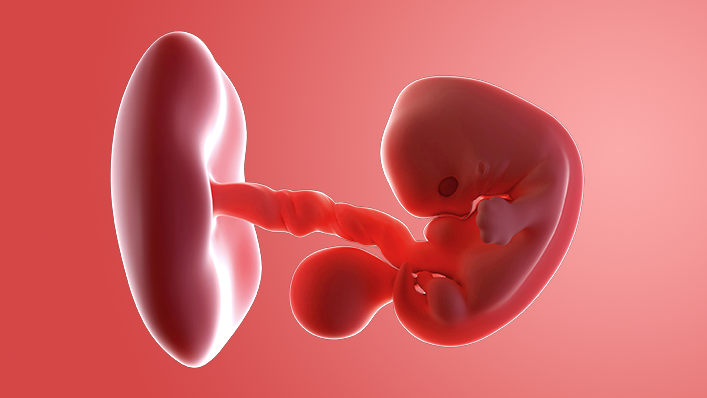

Your baby, or embryo, is about 2mm long (about the size of a poppy seed) and growing rapidly in your womb.

It's protected by an amniotic sac, which is filled with cushioning fluid, and attached to a tiny yolk sac that provides all the nourishment it needs.

The outer layer will later develop into the placenta and provide your baby with oxygen and nutrients.